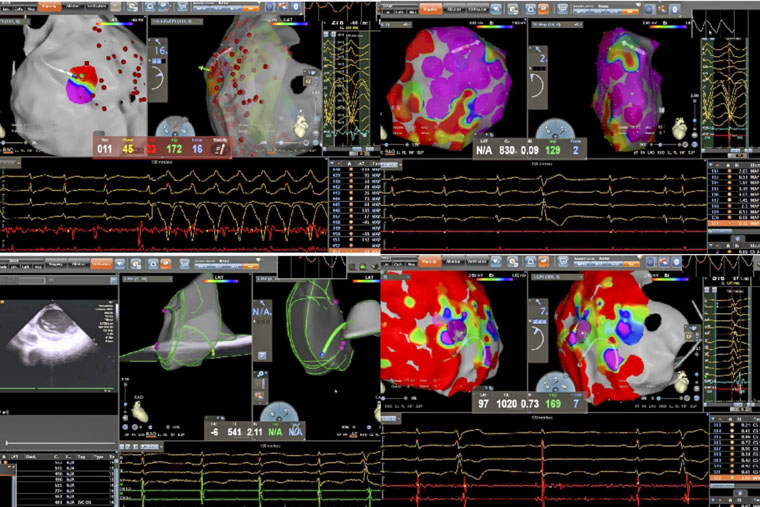

病理性室速通常指由器质性心脏病(如心肌梗死、心肌病等)所导致的室性心动过速。一名患者所患的ARVC,是一种以右心室心肌被纤维脂肪组织替代为特征的遗传性疾病,异常的心肌结构易形成异常电传导通路,从而引发药物难以控制的恶性室速,传统治疗难度大、复发率高。术中,手术团队在X线透视引导下施行心包穿刺,有效规避冠状动脉及心肌损伤风险,为心外膜途径消融建立安全通道。在此基础上,同步进行心内膜及心外膜高密度标测,于右心室多部位识别出低电压区、延迟电位等异常电活动特征,精准判定参与心动过速的关键区域,依托三维电生理标测系统,完成了心内膜与心外膜联合消融。

另一名患者为61岁男性,术前发现频发室性早搏(24小时超过10930次),部分呈三联律及短阵室速,心电图提示起源点为左室乳头肌。频发室早对即将接受大型癌症手术的患者构成多重威胁,如麻醉可能诱发恶性心律失常、室早会影响血流动力学稳定、心脏问题还可能延误肿瘤手术时机。心内科与胃肠外科、麻醉科迅速启动MDT讨论,一致认为必须在肿瘤手术前根除室早这一“定时炸弹”。团队即刻启用“电生理第三只眼”——心腔内超声(ICE)引导手术:ICE导管送入心腔,实时显示左室内乳头肌形态、位置及导管贴靠情况;在ICE引导下克服乳头肌移动难题,实现稳定贴靠与精准消融;ICE实时监测心包情况,极大避免并发症的发生。术后患者室早完全消失,心脏风险解除,并于次日顺利接受贲门癌根治术,现已康复出院。

姚铁柱副主任表示,两例手术的成功实施,共同依托于术前的充分评估与个体化方案设计,先进的影像引导技术(X线、三维标测、ICE)以及手术团队娴熟的技术配合与对心律失常机制的深刻理解。

器质性室速与复杂结构起源室早的消融,是心脏电生理领域的重要挑战。联合心内膜与心外膜途径的标测与消融,以及ICE引导下的精准操作,可显著提高此类复杂心律失常的治愈率,为药物无效、常规消融困难或合并多系统疾病的患者提供新的治疗途径。